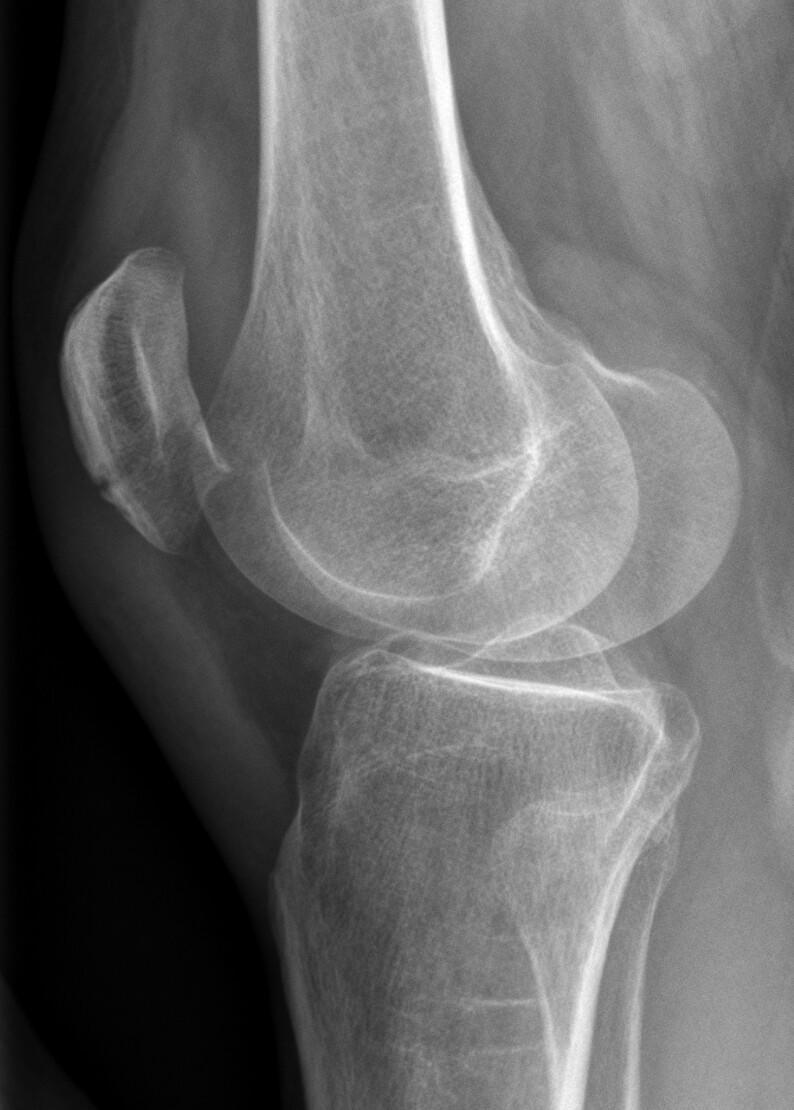

Fracture de patella

Hellerhoff - Own work, CC BY-SA 3.0, Link

Verticale : non déplacée

• Attelle de Zimmer 4 semaines avec appui autorisé

Horizontale ou multi parcellaire : avis chirurgical.